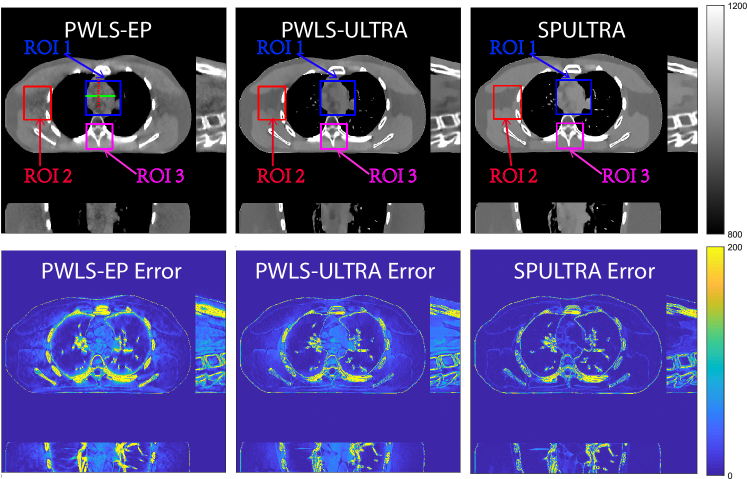

Fig. 4 shows the reconstructed images and the corresponding error images for PWLS-EP, PWLS-ULTRA, and SPULTRA, at and . Compared to the PWLS-EP result, both PWLS-ULTRA and SPULTRA achieved significant improvements in image quality in terms of sharper reconstructions of anatomical structures such as bones and soft tissues, and suppressing the noise. However, the PWLS-ULTRA method introduces bias in the reconstructions, which leads to larger reconstruction errors compared to the proposed SPULTRA method. In Fig. 4, we marked three 3D ROIs in the axial plane, i.e., ROI 1, ROI 2, and ROI 3. Fig. 5 shows the zoom-in images of a 3D plot of ROI 1, and those of ROI 2 and ROI 3 are shown in the supplement. We also plot the evolution of RMSE through the axial slices of the three 3D ROIs in Fig. 6. The figures demonstrate that SPULTRA clearly outperforms the competing PWLS-EP and PWLS-ULTRA schemes.

The above advantages of SPULTRA can be seen more clearly when observing the image profiles. Fig. 7 plots the image profiles for the three methods together with that of the ground-truth image. Fig. 4 shows the horizontal green solid line and the vertical red dashed line, whose intensities are plotted in Fig. 7. It is obvious that the profiles for SPULTRA are closest to the ground-truth among the three compared methods. The gap between the profiles of the PWLS-based methods and the ground-truth shows the bias caused by the compared PWLS methods.